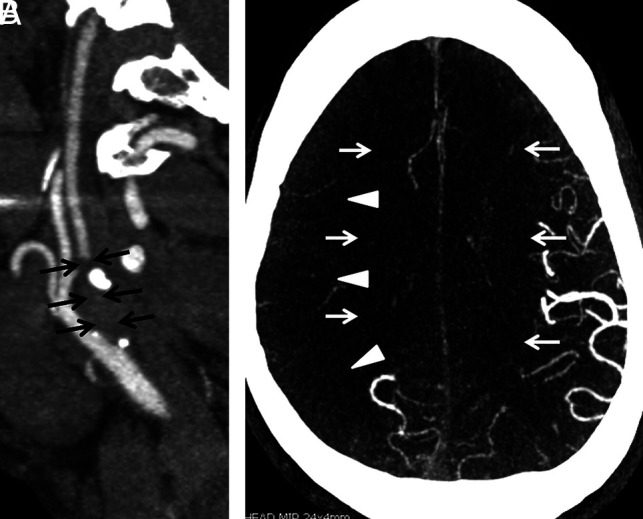

FIG 2.

A, Sagittal MIP image from the extracranial CTA performed on the day of admission demonstrates a segmental high-grade stenosis of the proximal right internal carotid artery (arrows). There is normal flow in the right common carotid and external carotid arteries. B, Axial MIP of the intracranial CTA performed on the day of admission demonstrates markedly decreased vascular flow within the branches of the right MCA (arrowheads) and bilateral ACAs (arrows). Conversely, there is normal vascular flow in the left MCA and bilateral posterior cerebral artery territories.